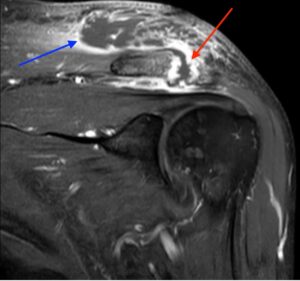

Septic Arthritis of AC Joint. MRI Coronal. Annotated. JETem 2024